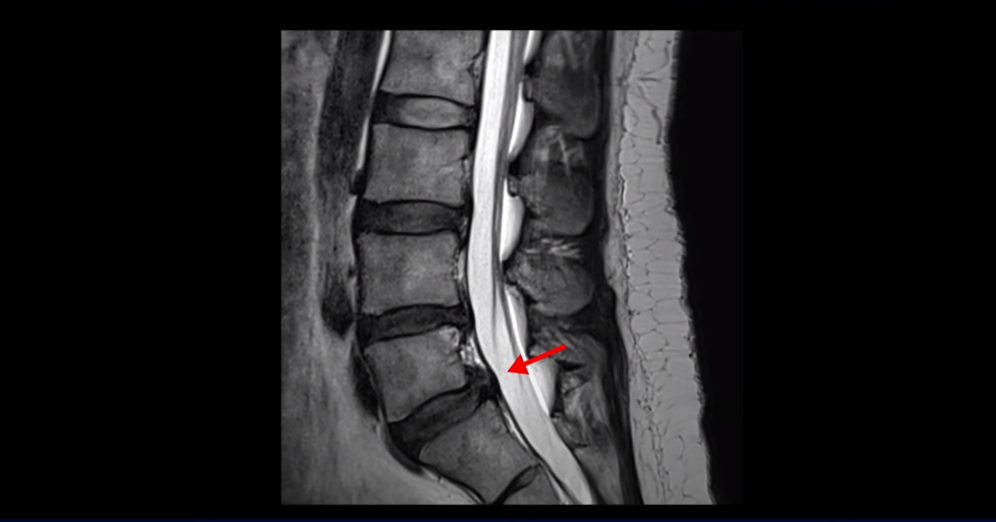

무거운 물건을 들다가 갑자기 심한 허리 통증 및 오른쪽 다리 방사통과 함께 오른쪽 고관절, 무릎, 발목에 운동 마비가 발생했습니다. 왼쪽 다리와 발은 움직이는데 오른쪽 다리와 발은 움직임이 전혀 없습니다. 문제는 이분 MRI를 보면 디스크 탈출이 심해 보이지 않습니다.

가운데 우측으로 파열도 아닌 돌출 정도의 탈출만 있습니다.

추간공도 충분히 열려 있는 상태입니다.

누가 봐도 이 정도 디스크로는 심한 마비가 올 수 없는 상태입니다. 근전도도 정확하게 마비의 원인이 허리에 있다고 설명하지 못했습니다. 그러니까 어느 병원도 수술을 자신 있게 하라고 얘기를 못 하고 마비가 왔으니까 그래도 수술을 해 보는 게 낫지 않겠냐고 얘기합니다.

그런데 이 환자분의 X-ray를 보면 척추분리증으로 인한 전방전위증과 불안정성이 있습니다.

허리를 구부렸다 폈다 할 때 허리 신경 공간의 변화가 있음을 유추해 볼 수 있습니다.